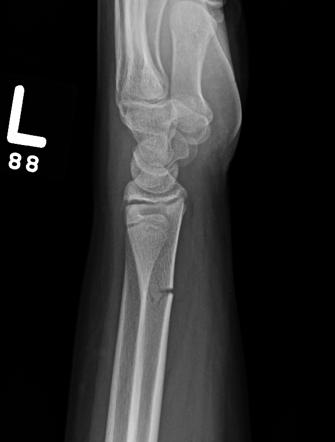

Can you find the fracture?

Q2

An avulsion fracture of the patella (knee cap)

A colles fracture of the head of the radius and ulna. Understand exactly what this is here